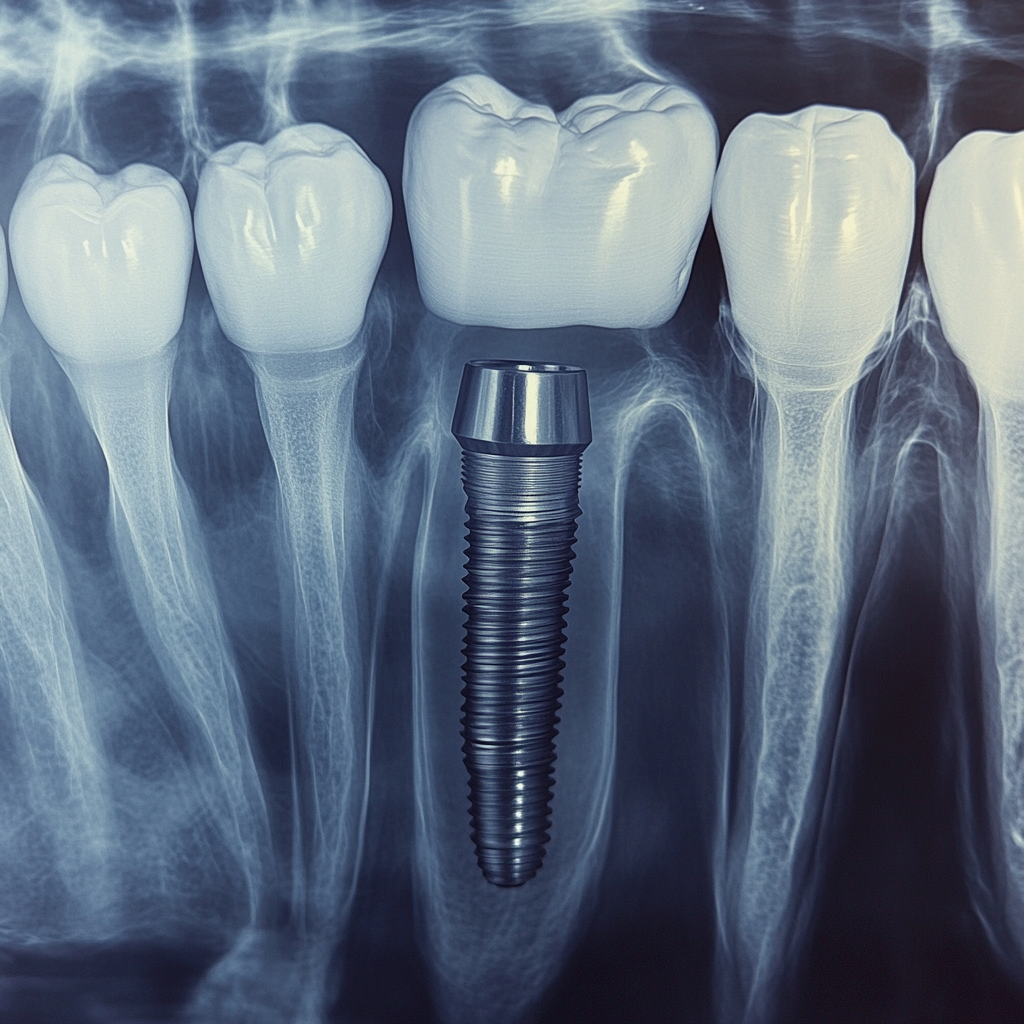

Si vous avez commencé à ressentir des douleurs autour de votre implant dentaire plusieurs années après l’intervention, la première chose à faire est de consulter votre dentiste dès que possible. Il prendra probablement des radiographies pour évaluer l’état de l’implant, de l’os environnant et du tissu gingival. Dans de nombreux cas, un nettoyage professionnel en profondeur et la prise d’antibiotiques permettent de résoudre des infections mineures avant qu’elles ne causent de graves dommages.

Si une perte osseuse est détectée, votre dentiste peut envisager une greffe osseuse pour rétablir la stabilité. Il s’agit d’une procédure plus complexe, mais dans de nombreux cas, elle peut sauver un implant de l’échec.